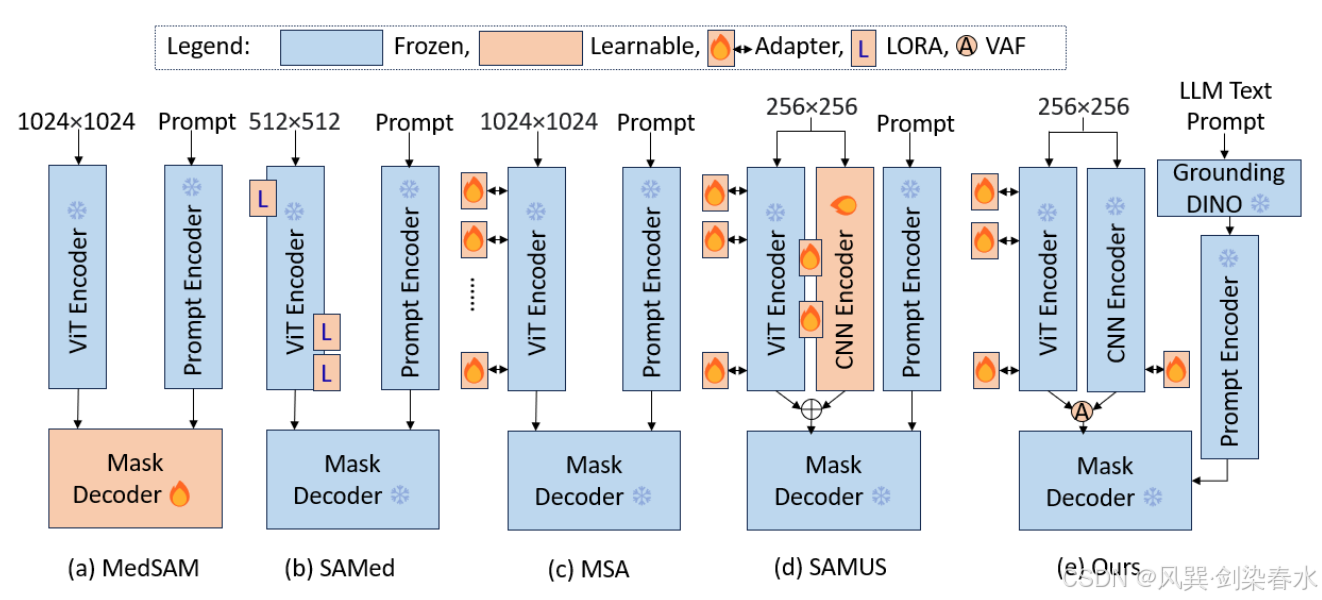

Figure 1 | 使用SAM进行医学图像分割的方法比较: